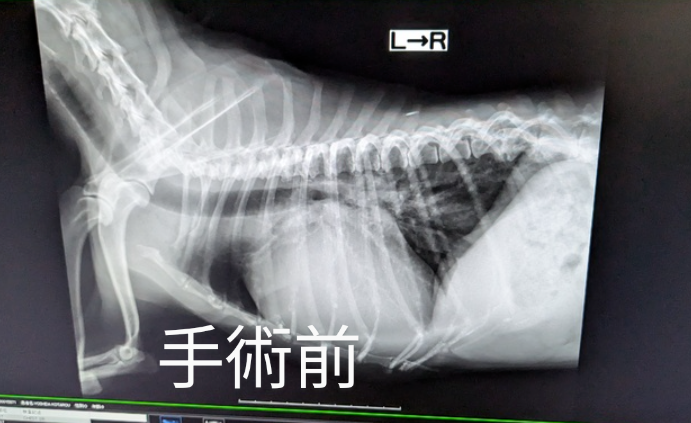

半年検診です🏥

月日が経つのは早いもので半年検診となりました。虎太郎は退院後も何かしらの懸念点があった為に小刻みな検査でしたが2ヶ月空くと久々な感じがありますね🙃

結果でいうと良い所と悪い所がありまして、良くなったのは心臓のサイズが縮んでおりました。4ヶ月検診の頃はこれ以上縮むのはないかなぁという温度感だったのですが、3ヶ月前と比べて結構縮んでおりました✨